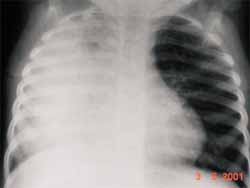

Las consolidaciones multilobares también pueden ocurrir (Figura 8), sin embargo, la consolidación total de un pulmón es rara y la opacificación total de un hemitorax es más usualmente secundaria a empiema.

FIGURA 8. Paciente lactante de sexo femenino con neumonía por neumococo, observe el componente

multilobar con compromiso casi de la totalidad del hemitórax derecho.